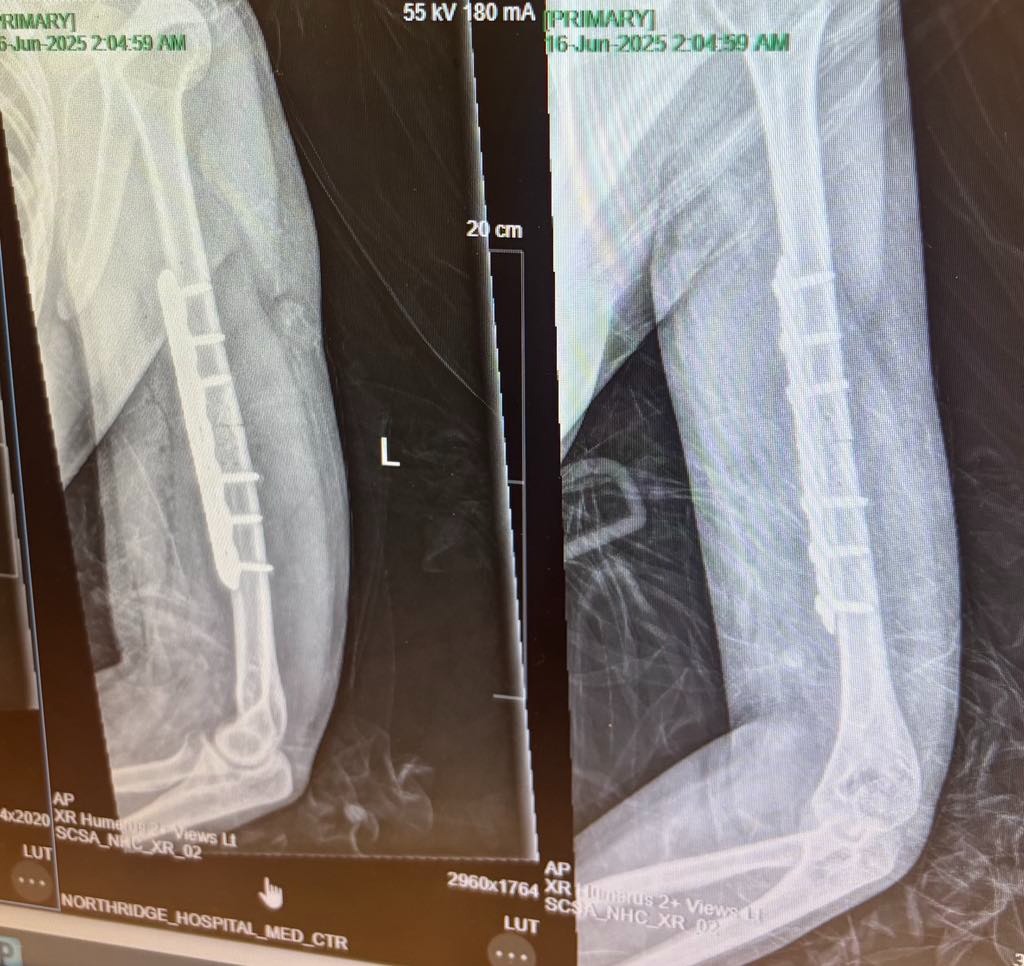

On Saturday, June 14th, 17-year-old Paisley Nicholl was a passenger in a tragic car accident that left her with serious injuries. Paisley suffered a broken humerus (upper arm) and a fractured hip, requiring a six-hour surgery to insert metal rods into both bones. The surgery took place at Northridge Hospital, but Paisley’s road to recovery is just beginning.